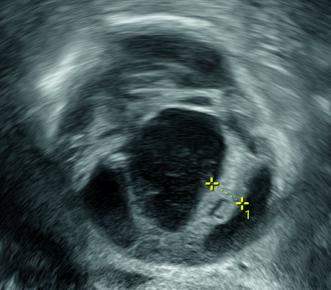

Während der Laparoskopie zeigte sich ein unauffälliger Situs bei Status nach Hysterektomie. Überraschenderweise waren auch die Ovarien makroskopisch unauffällig. In der rechten Fossa obturatoria hingegen fiel eine retroperitoneal gelegene Vorwölbung auf, welche bei Füllung der Harnblase gut von dieser abgrenzbar blieb (Abb. 2). Nach Durchführung einer Spülzytologie sowie der beidseitigen Adnexektomie folgte die Präparation dieser Raumforderung, welche in der Fossa obturatoria gelegen war. Der Tumor war mit dem N. obturatorius verwachsen (Abb. 3). Ein Ursprung aus dem Nerv schien nicht ausgeschlossen. Unter Erhaltung eines möglichst grossen Anteils des N. obturatorius wurde die Raumforderung vorsichtig in toto entfernt.

Postoperativ zeigte sich ein erfreulicher Verlauf, insbesondere waren keine motorischen oder sensorischen Einschränkungen festzustellen. Die Ovarien waren auch bei der histopathologischen Aufarbeitung unauffällig. Bei der Raumforderung handelte es sich um ein Schwannom des N. obturatorius, welches sich zwar mit deutlich regressiv veränderten Anteilen präsentierte, jedoch ebenfalls keine Hinweise auf eine Malignität zeigte.